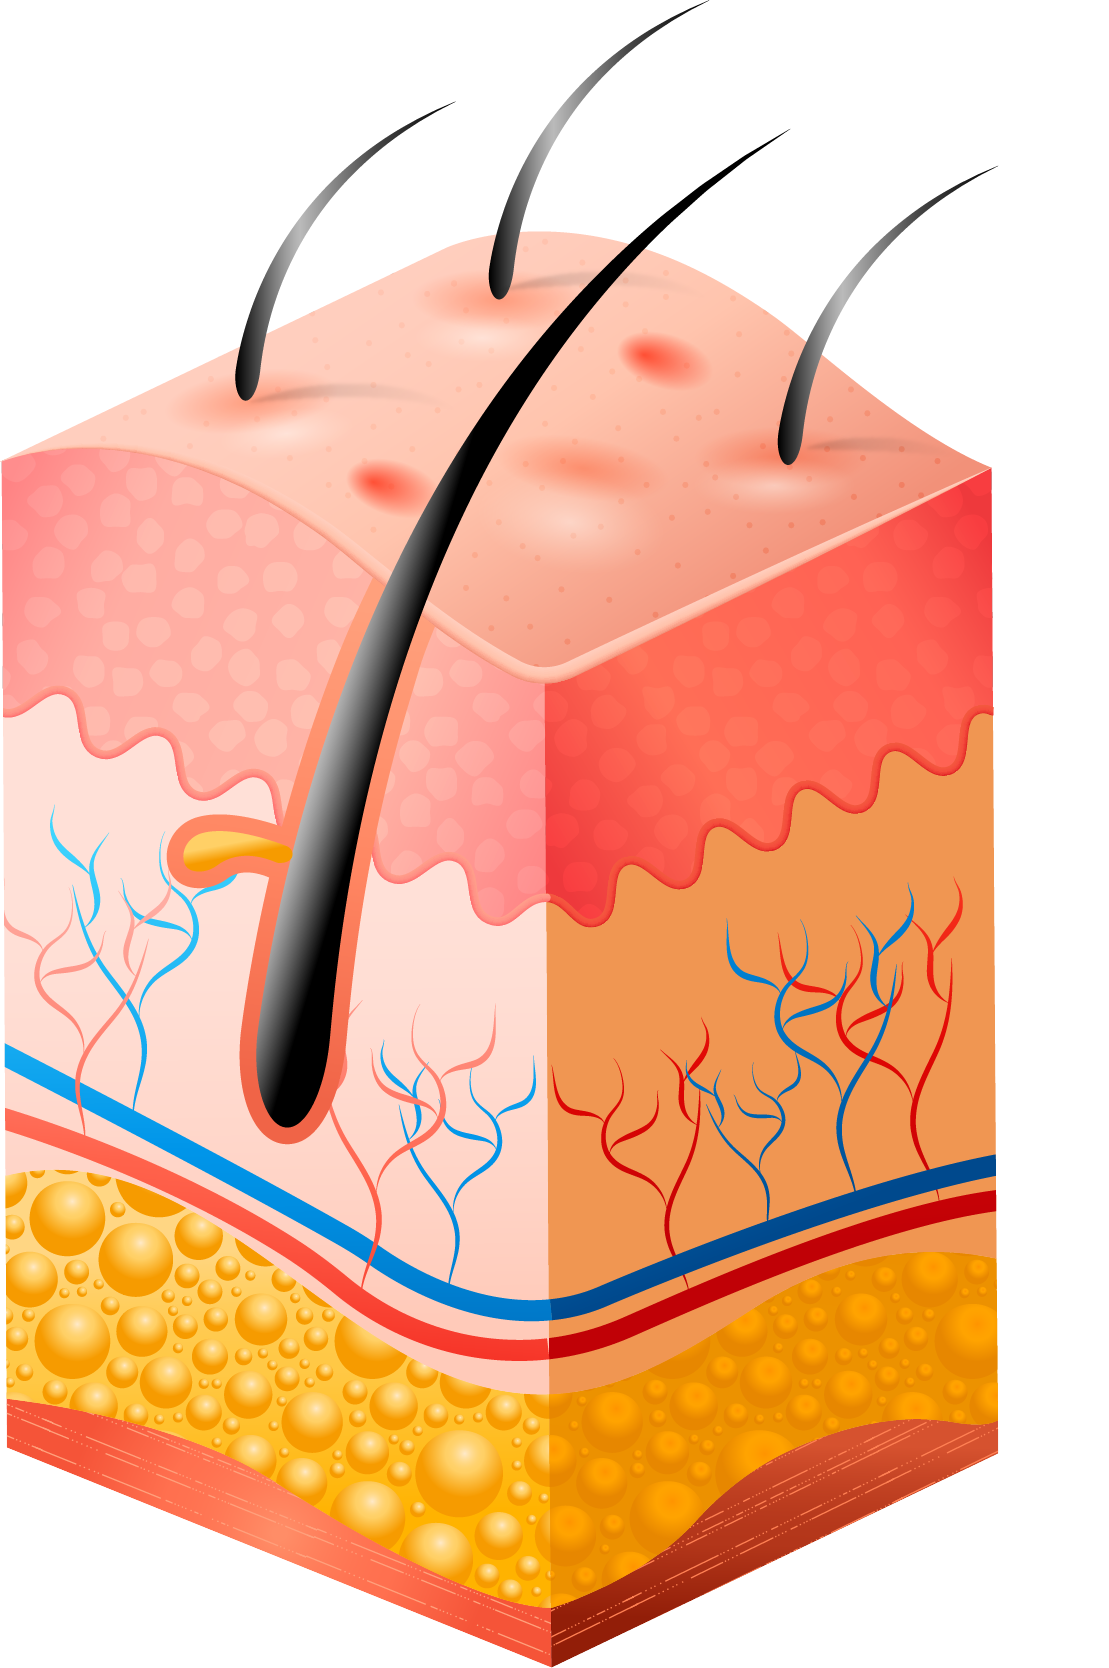

PAHs and PCBs damage the layer of the skin leading to:

PAHs and PCBs damage the layer of the skin leading to: